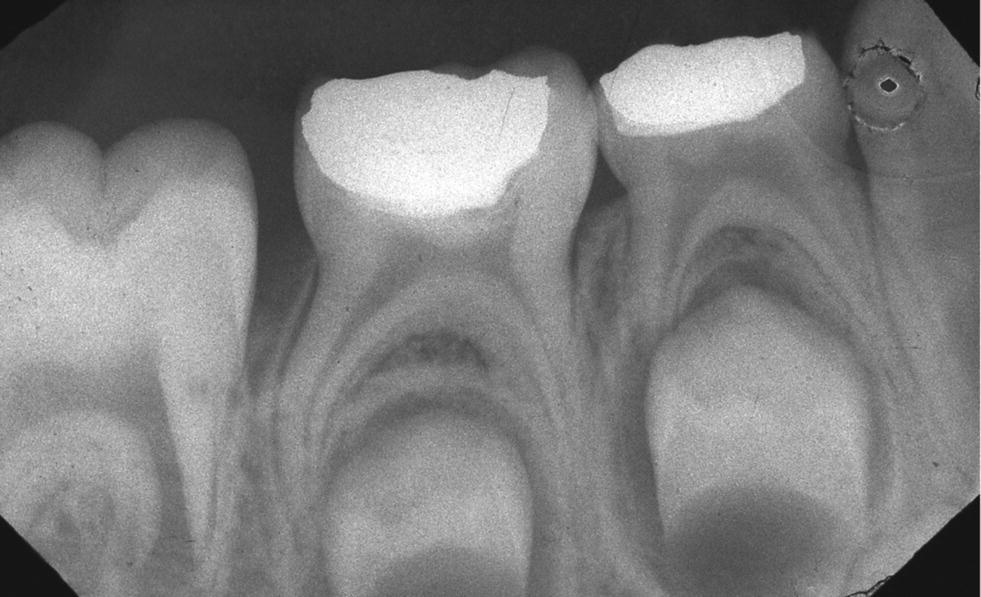

Initial view. Right mandibular first molar with endodontic treatment

Initial view. Right mandibular first molar with endodontic treatment Endodontic Treatment Primary Molars Systematic literature synthesis shows that endodontic treatment of molars, due to its larger number of roots, is more difficult than those of. The selected studies included 283 primary molars, of 213 children aged between 3 and 9 years, treated by niet and conventional. Emphasises the anatomy of molar teeth in relation to endodontic treatment. Endodontic treatment in primary teeth can. Endodontic Treatment Primary Molars.